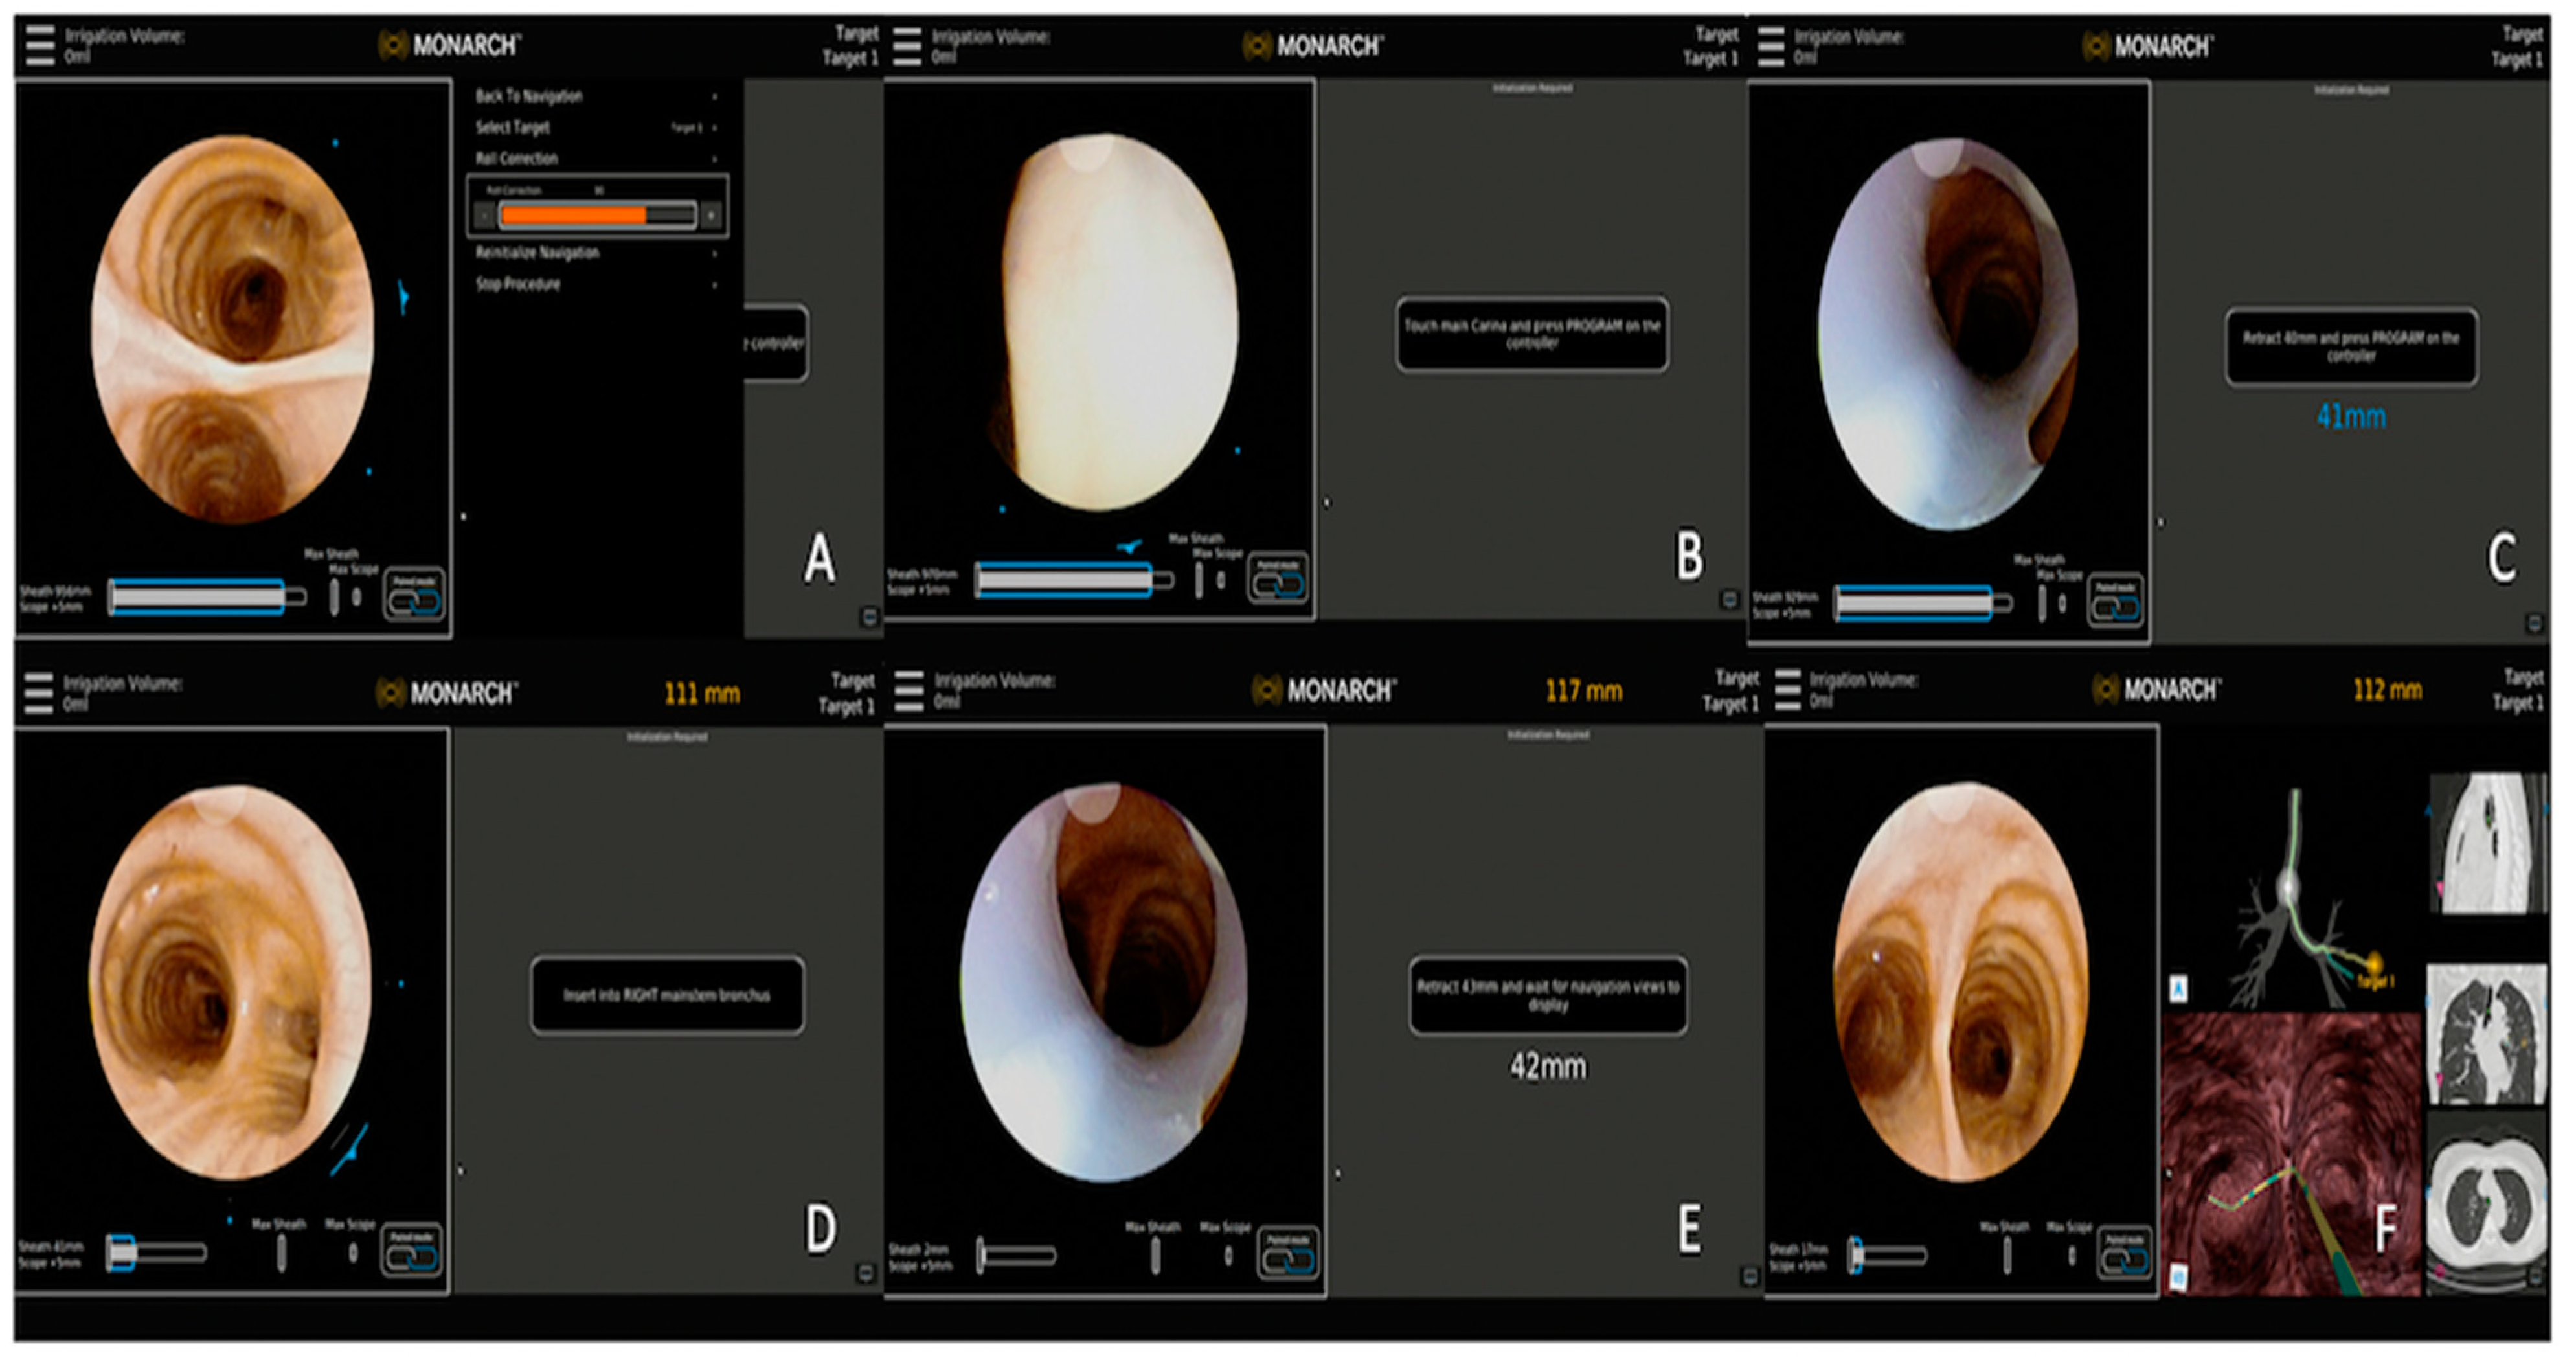

3.2.2. Monarch™ Robotic Platform Combined with CBCT

| Hedstrom et al. [19] | Monarch™ robotic platform with lung vision | Robotic platform for navigation with CABT from Lung vision for intra-procedural real-time guidance | 45 patients | DYi: 84% DA: 91% | Pneumothorax: 8% (4/45) |